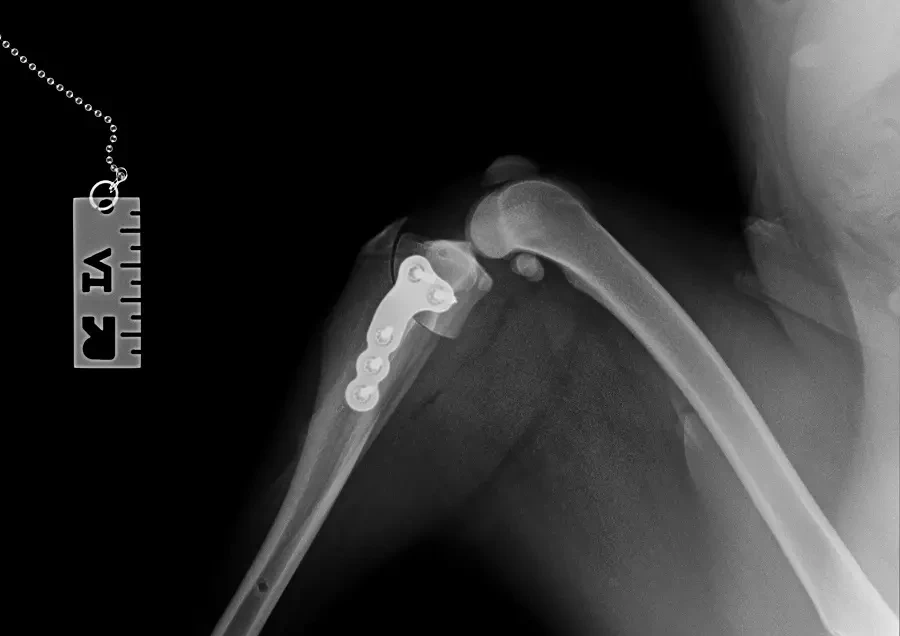

Zerwanie więzadła krzyżowego doczaszkowego jest jedną z najczęstszych przyczyn wizyt w zakładach leczniczych z powodu kulawizny u psów. Cele tego artykułu to:…

Zerwanie więzadła krzyżowego do czaszkowego jest jedną z najczęstszych przyczyn wizyt w zakładach leczniczych z powodu kulawizny u psów. Celem tego artykułu…